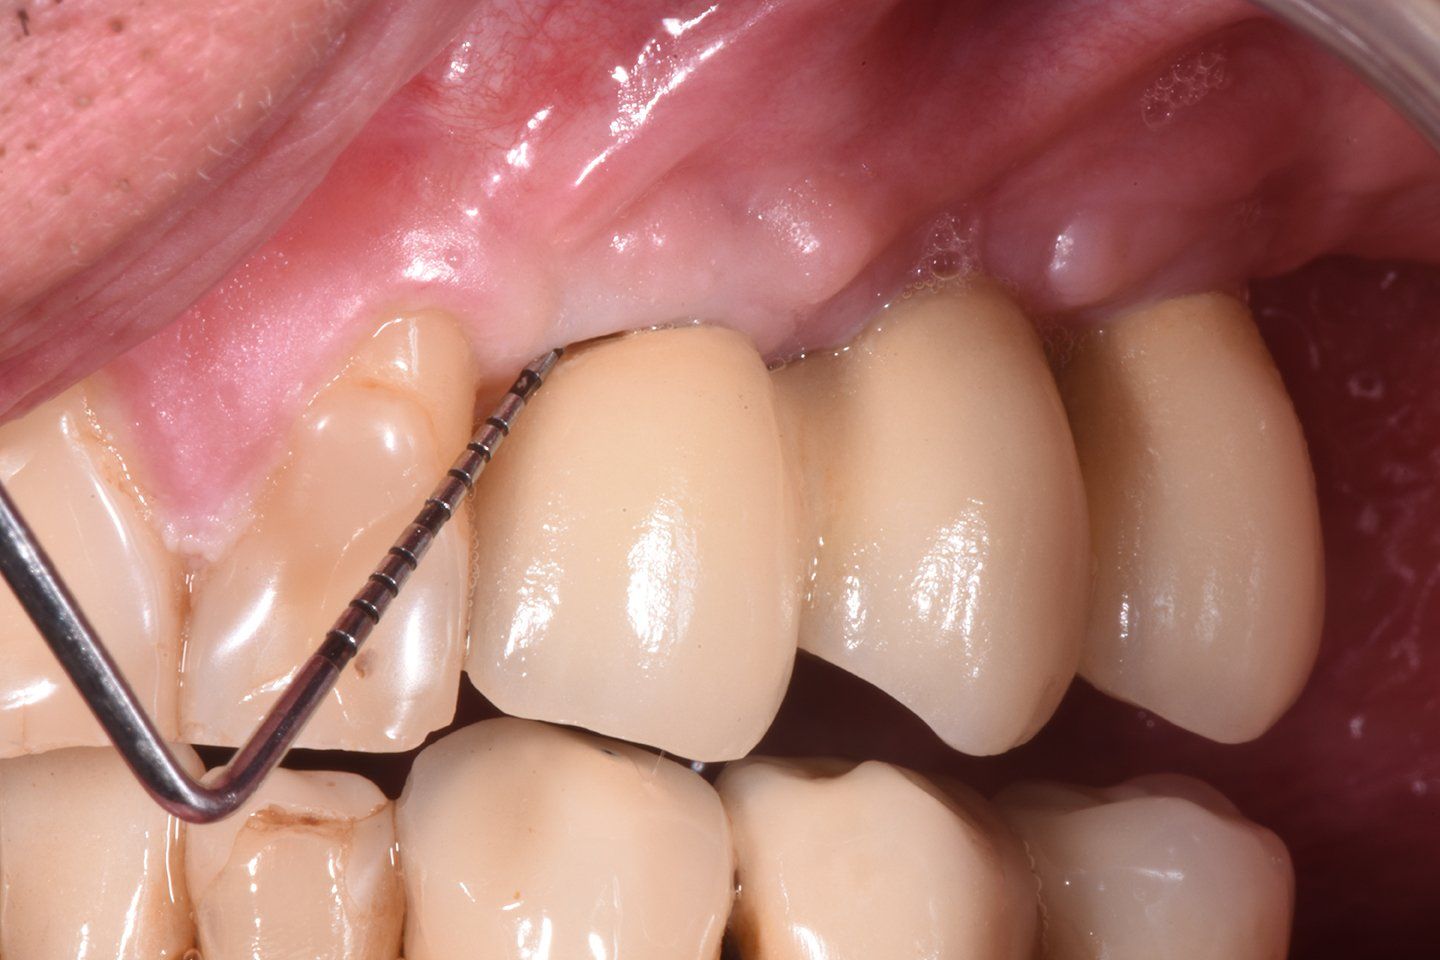

Il paziente selezionato per questo case report presenta 2 impianti dentali posizionati 4 anni prima in zona 23 e 25. Sono evidenziati al momento del primo appuntamento (T0) i segni clinici di mucosite con sanguinamento abbondante al sondaggio, presenza di gengiva infiammata e placca, mancanza di segni radiografici con perdita di osso marginale maggiore di 2 mm.

Il paziente, uomo di 55 anni non presenta nessuna patologia sistemica, non fuma e non assume farmaci in modo abitudinario, ma presenta dei segni clinici di infiammazione a livello del manufatto implanto-protesico su 2.3, nessun segno radiografico rilevante (Fig. 1).

Al primo appuntamento (T0) il paziente è stato visitato e sono stati rilevati i dati clinici, anamnesti e radiografici. L’anamnesi è negativa per patologie sistemiche. Una volta accertata la presenza di mucosite sull’elemento 2.3 al paziente vengono fornite le istruzioni per una terapia reattiva domiciliare, ovvero si consiglia l’uso di spazzolino con setole morbite unito ad un agente antimicromico e anti-infiammatorio, in questo caso a base di Nitradine. In particolare, la confezione di PerioTabs®, consiste di 10 compresse a base di NitrAdine® e un dosatore (Fig. 2). Tutte le sere per dieci giorni, dopo aver effettuato la normale igiene interprossimale con gli scovolini, il paziente deve far sciogliere una di queste compresse in un bicchiere con il dosatore pieno di acqua tiepida (Fig. 3), e immergere il nuovo spazzolino nella soluzione per circa dieci minuti, affinché le setole assorbano la soluzione (Fig. 4). Dopodiché, dovranno spazzolare denti e gengive nella zona da trattare, senza utilizzare dentifricio, per almeno due minuti (Fig. 5). Dopo il trattamento si risciacqua abbondantemente con acqua. Lo spazzolino deve essere usato per dieci giorni, alla sera, secondo le indicazioni riportate sulla confezione PerioTabs®, mentre al mattino i pazienti spazzoleranno i denti senza alcun dentifricio o soluzione (Fig. 6).

Dopo sette giorni dalla prima visita e dalle istruzioni all’igiene domiciliare (T1), i pazienti vengono richiamati per la terapia professionale non chirurgica, prima della quale vengono nuovamente registrati tutti i parametri clinici.

La FMD nel primo paziente, affetto da mucosite perimplantare a livello di due elementi, consiste in una prima fase di deplaquing con ablatore ad ultrasuoni con inserto in peek, per evitare di alterare la superficie dell’impianto o della corona, e in una seconda fase di air-polishing sopragengivale con polvere AIR-FLOW® powder PLUS a base di eritritolo contenente lo 0,3% di clorexidina, a granulometria di 14 μm, con un tempo di applicazione di 5 secondi per ogni sito facendo piccoli movimenti verticali e orizzontali. È stato, infine, applicato un gel parodontale a base di clorexidina allo 0.5%, enoxolone e acido ialuronico (Plak gel active 0,5% Emoform) a livello del margine gengivale dei siti trattati e due cicli di acqua ozonizzata da 1,5 minuti mediante irrigatore professionale19.

Dopo trenta giorni (T2) dalla prima seduta (T0), i pazienti tornano in studio per rivalutare i parametri clinici. Si può subito notare, clinicamente che il risultato estetico e l’aspetto clinico della salute tissutale è evidente a T2 come a T1 nonostante i giorni trascorsi. Una terapia non chirurgica suddivisa da un approccio domiciliare reattivo iniziale consente agli operatori di lavorare con maggiore predicibilità, ottimi risultati estetici e minimo dolore per il paziente; inoltre una terapia di supporto post-trattamento consente di mantenere il risultato di salute ottenuto nel tempo21.